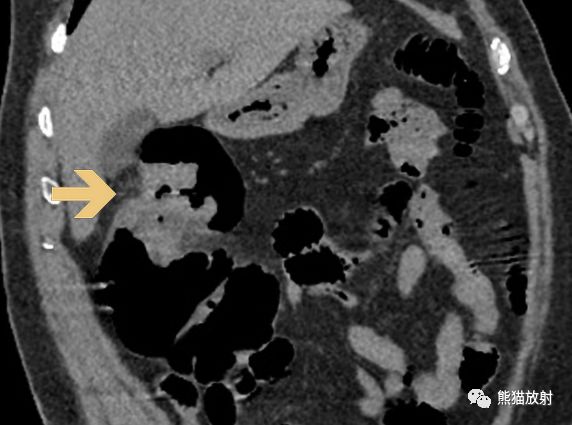

在CT图像上同样可以有苹果核征的表现。

横结肠癌CT表现及大体病理: